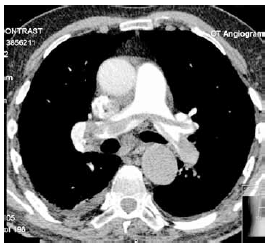

Considere a angiotomografia de tórax com contraste a seguir.